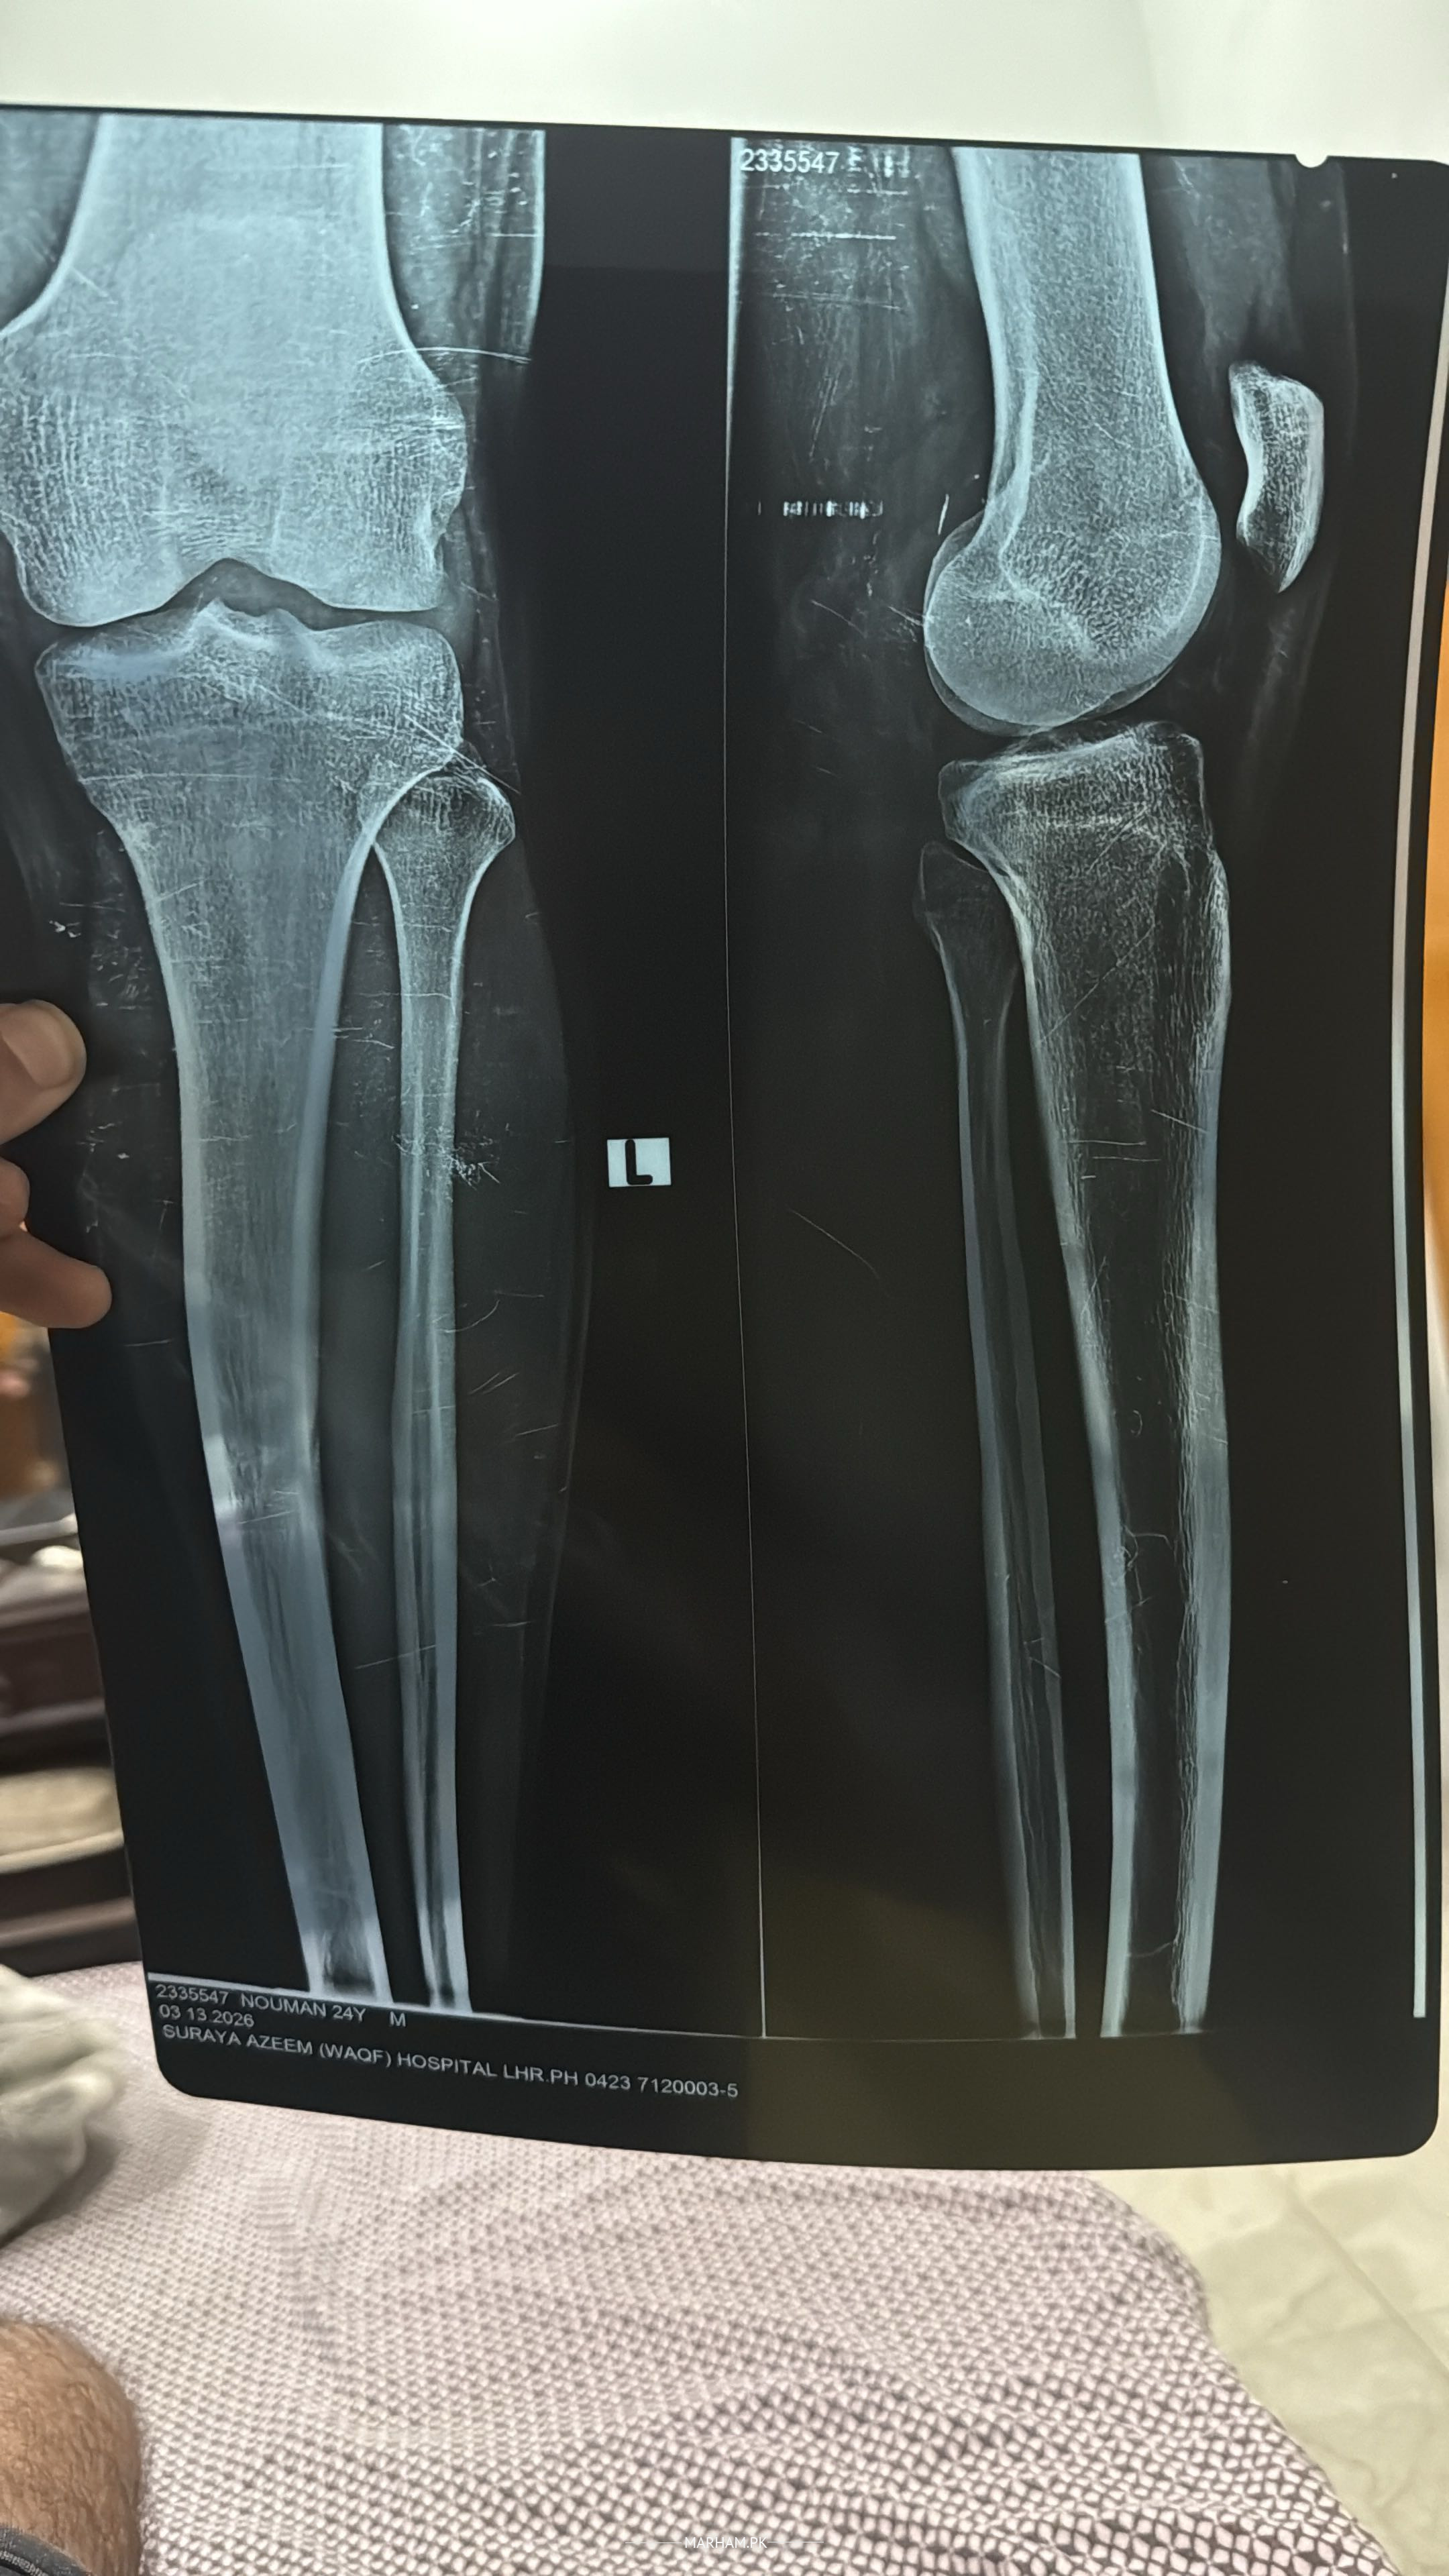

The X-ray image you shared shows both knees (likely an AP and lateral view, or bilateral comparison) of what appears to be a 24-year-old male patient (based on the label: "NOUMAN 24Y M", dated around March 2025).

Key observations from the visible radiograph:

- The overall alignment of the femur, tibia, and fibula looks normal on both sides — no obvious angulation, displacement, or shortening that would suggest a fresh acute fracture of the long bones.

- The knee joint spaces appear preserved (no severe narrowing).

- No clear evidence of a complete tibial plateau fracture, distal femur fracture, or obvious patellar issues in the main views shown.

- However, there is a **small bony fragment visible near the lateral aspect of the right knee** (on the viewer's left side of the image, appearing as a separate small piece of bone just proximal/lateral to the tibial plateau/fibular head region).

This detached fragment is the most notable abnormality. It could represent one of the following (most likely in rough order of probability):

1. **Avulsion fracture** — commonly from the **fibular head** (e.g., arcuate ligament avulsion) or **lateral tibial plateau** (Segond-like fragment, though classic Segond is more anterior). Often associated with ACL injury, posterolateral corner injury, or twisting/varus stress.

2. **Chip fracture** from the proximal tibia or fibula due to direct trauma.

3. Less likely: old ununited fragment, loose body, or calcified structure (but appearance favors acute/subacute bone piece).

The rest of the bones look intact without obvious cortical breaks, step-offs, or comminution in the main shafts or articular surfaces.

You wrote "Leg is fine" — if this refers to no major long-bone fracture or gross instability, that's reasonable. However, the small avulsion/chip fragment is **not normal** and usually indicates some degree of ligamentous injury (especially posterolateral corner or ACL/PCL-related in many cases).

**Recommendation** (not medical advice — please consult the treating orthopedic doctor):

- This finding typically warrants **MRI of the knee** to evaluate ligaments (ACL, PCL, collaterals, posterolateral corner), menisci, and cartilage — X-ray alone misses soft-tissue damage.

- Clinical correlation is essential: pain location, swelling, instability, mechanism of injury (twist? fall? sports?), ability to bear weight, etc.

- If there's locking, giving way, significant swelling, or positive clinical tests (e.g., varus stress, dial test), it becomes more urgent.

If you can share more details (symptoms, how the injury happened, or doctor's initial comment), or if this X-ray is yours/your family member's, I can try to help narrow it down further. In any case, follow up with an orthopedic specialist — small fragments like this are often important clues to bigger soft-tissue problems. Take care!